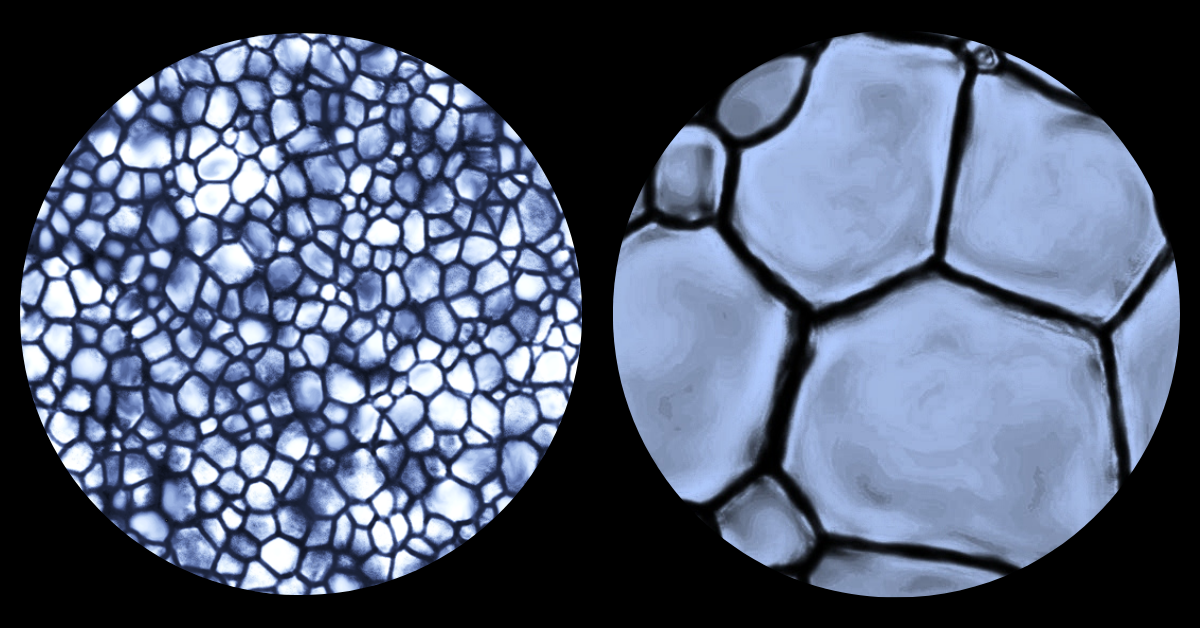

Des cristaux de glace à l'échelle d'un microscope ; petits cristaux de glace à gauche, et plus gros cristaux de glace à droite.

La formation de glace, ou recristallisation, est un effet inévitable de la congélation. Avec le temps et les fluctuations de température, les cristaux de glace deviennent de plus en plus gros, ce qui endommage la membrane de nombreuses cellules et provoque leur détérioration ou leur mort.

« Les petits cristaux ne posent pas de problème. Ils sont comme des grains de sable sur une plage des Caraïbes. Ils sont si petits qu’ils se moulent à votre corps; vous pouvez ainsi passer toute la journée à paresser sur la plage sans ressentir d’inconfort. Imaginons maintenant que vous vous étendez sur des galets ou du gravier. C’est loin d’être aussi confortable. Notre procédé de cryoconservation empêche donc les cristaux de devenir trop gros. »